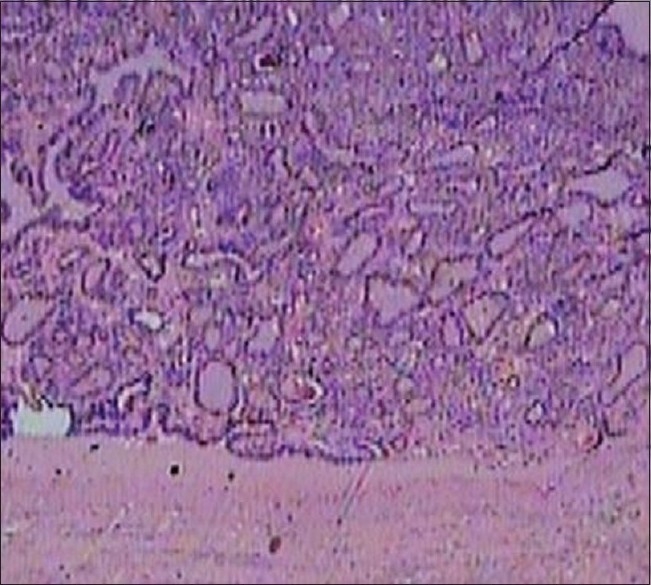

Fine needle biopsy of the swelling was reported as benign hyper plastic thyroid nodule. Her serum calcitonin level was normal. Left hemithyroidectomy was done. Frozen section examination of the nodule was reported as benign hyper plastic thyroid nodule, surprisingly, however, the final histology report was of a differentiated nodular papillary thyroid carcinoma in the excised thyroid nodule and rest of the lobe and isthmus were normal [Figure 3].

| Figure 3 Histopathology of the nodule showing well differentiated thyroid papillary carcinoma, H and E stain, ×10